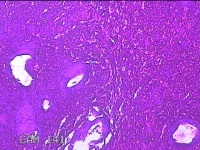

宫腔内容物

性别

女

年龄

40岁

临床诊断

异常子宫出血 子宫内膜息肉

一般病史

同房后出血3月。

标本名称

大体所见

灰白粉红色不规则碎组织3.5x3x0.8cm一堆。

图2